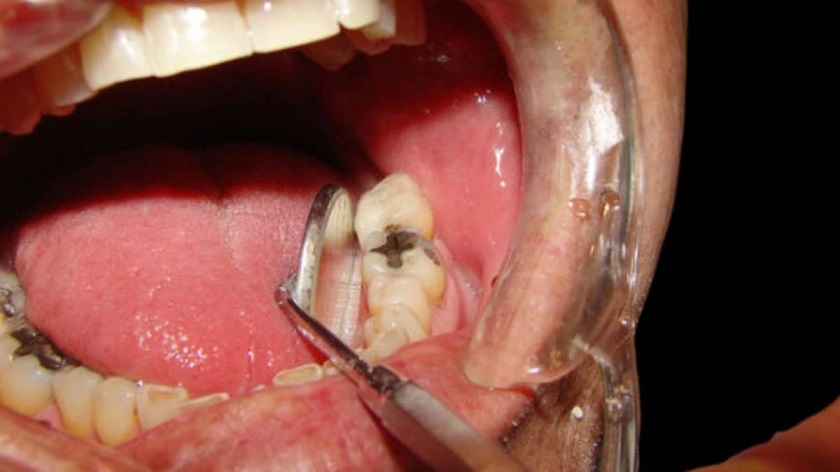

Những bệnh lý như sâu răng, viêm nướu, viêm nha chu… cũng cần phải được điều trị dứt điểm trước khi bọc răng sứ. Nếu không vi khuẩn sẽ tiếp tục tấn công sâu vào phần tủy răng, gây ra nhiễm trùng, áp xe hoặc tệ hơn là rụng răng.

Nếu bác sĩ không có đử kiến thức chuyên môn và tay nghề kém, thiếu kinh nghiệm, thì khi thực hiện phục hình răng sứ sẽ dễ xảy ra những sai sót. Như tỷ lệ mài răng sai, xâm lấn quá nhiều vào cấu trúc răng thật hoặc gắn răng sứ lệch với khớp cắn, gây chèn ép phần cùi răng và những răng bên cạnh. Tình trạng đau răng sau bọc răng sứ, ê buốt răng là không thể tránh khỏi.